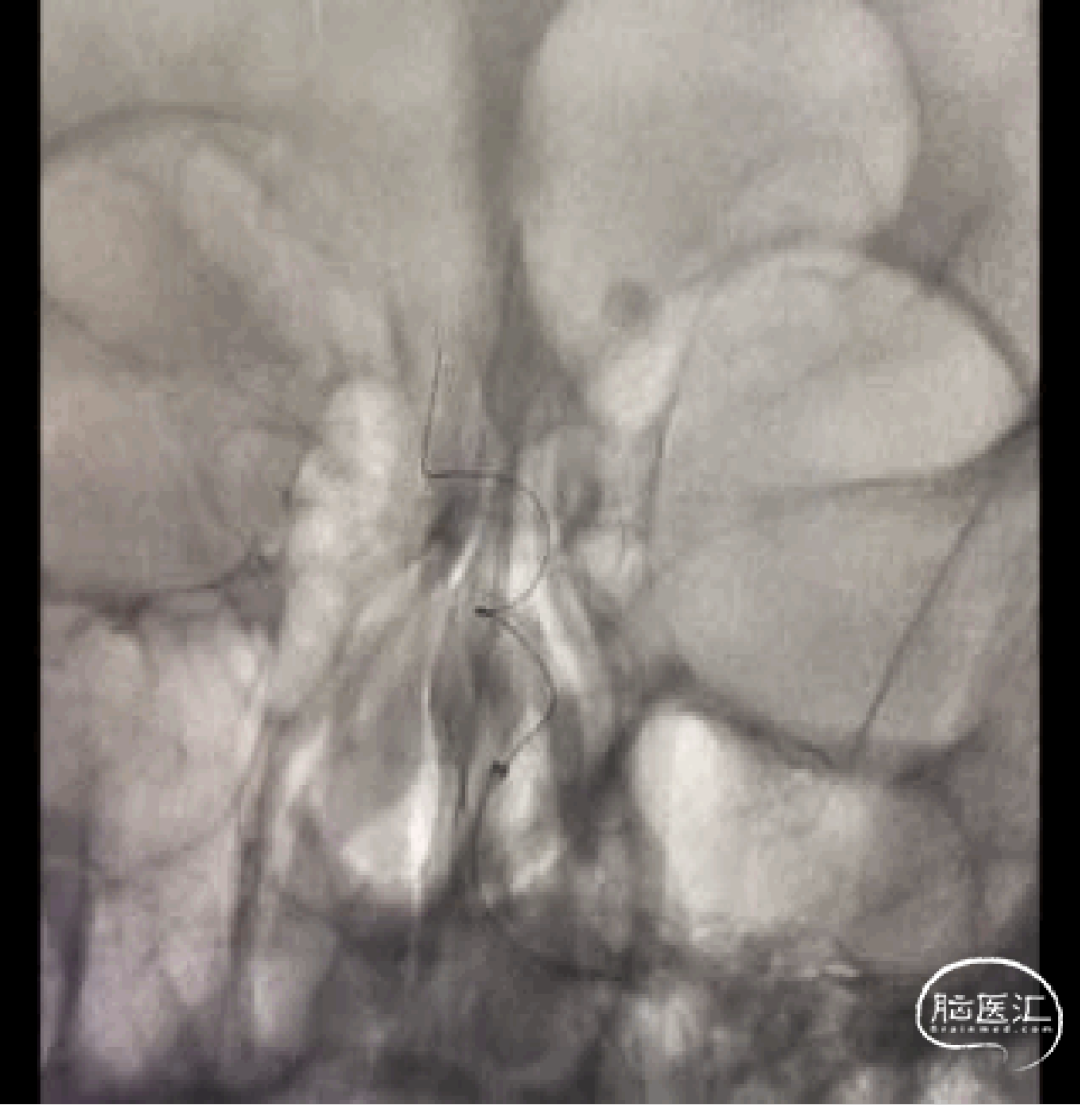

小血管血栓取栓病例

注:本文内容由赵宝元整理,其中部分病例作者详见下文。

作者:江苏泰州丁鸭锁、孙兵、尹春等。

一例左侧大脑中动脉M3段闭塞远端

抽吸导管血管再通治疗

作者:高军、温昌明

视频动图如下: